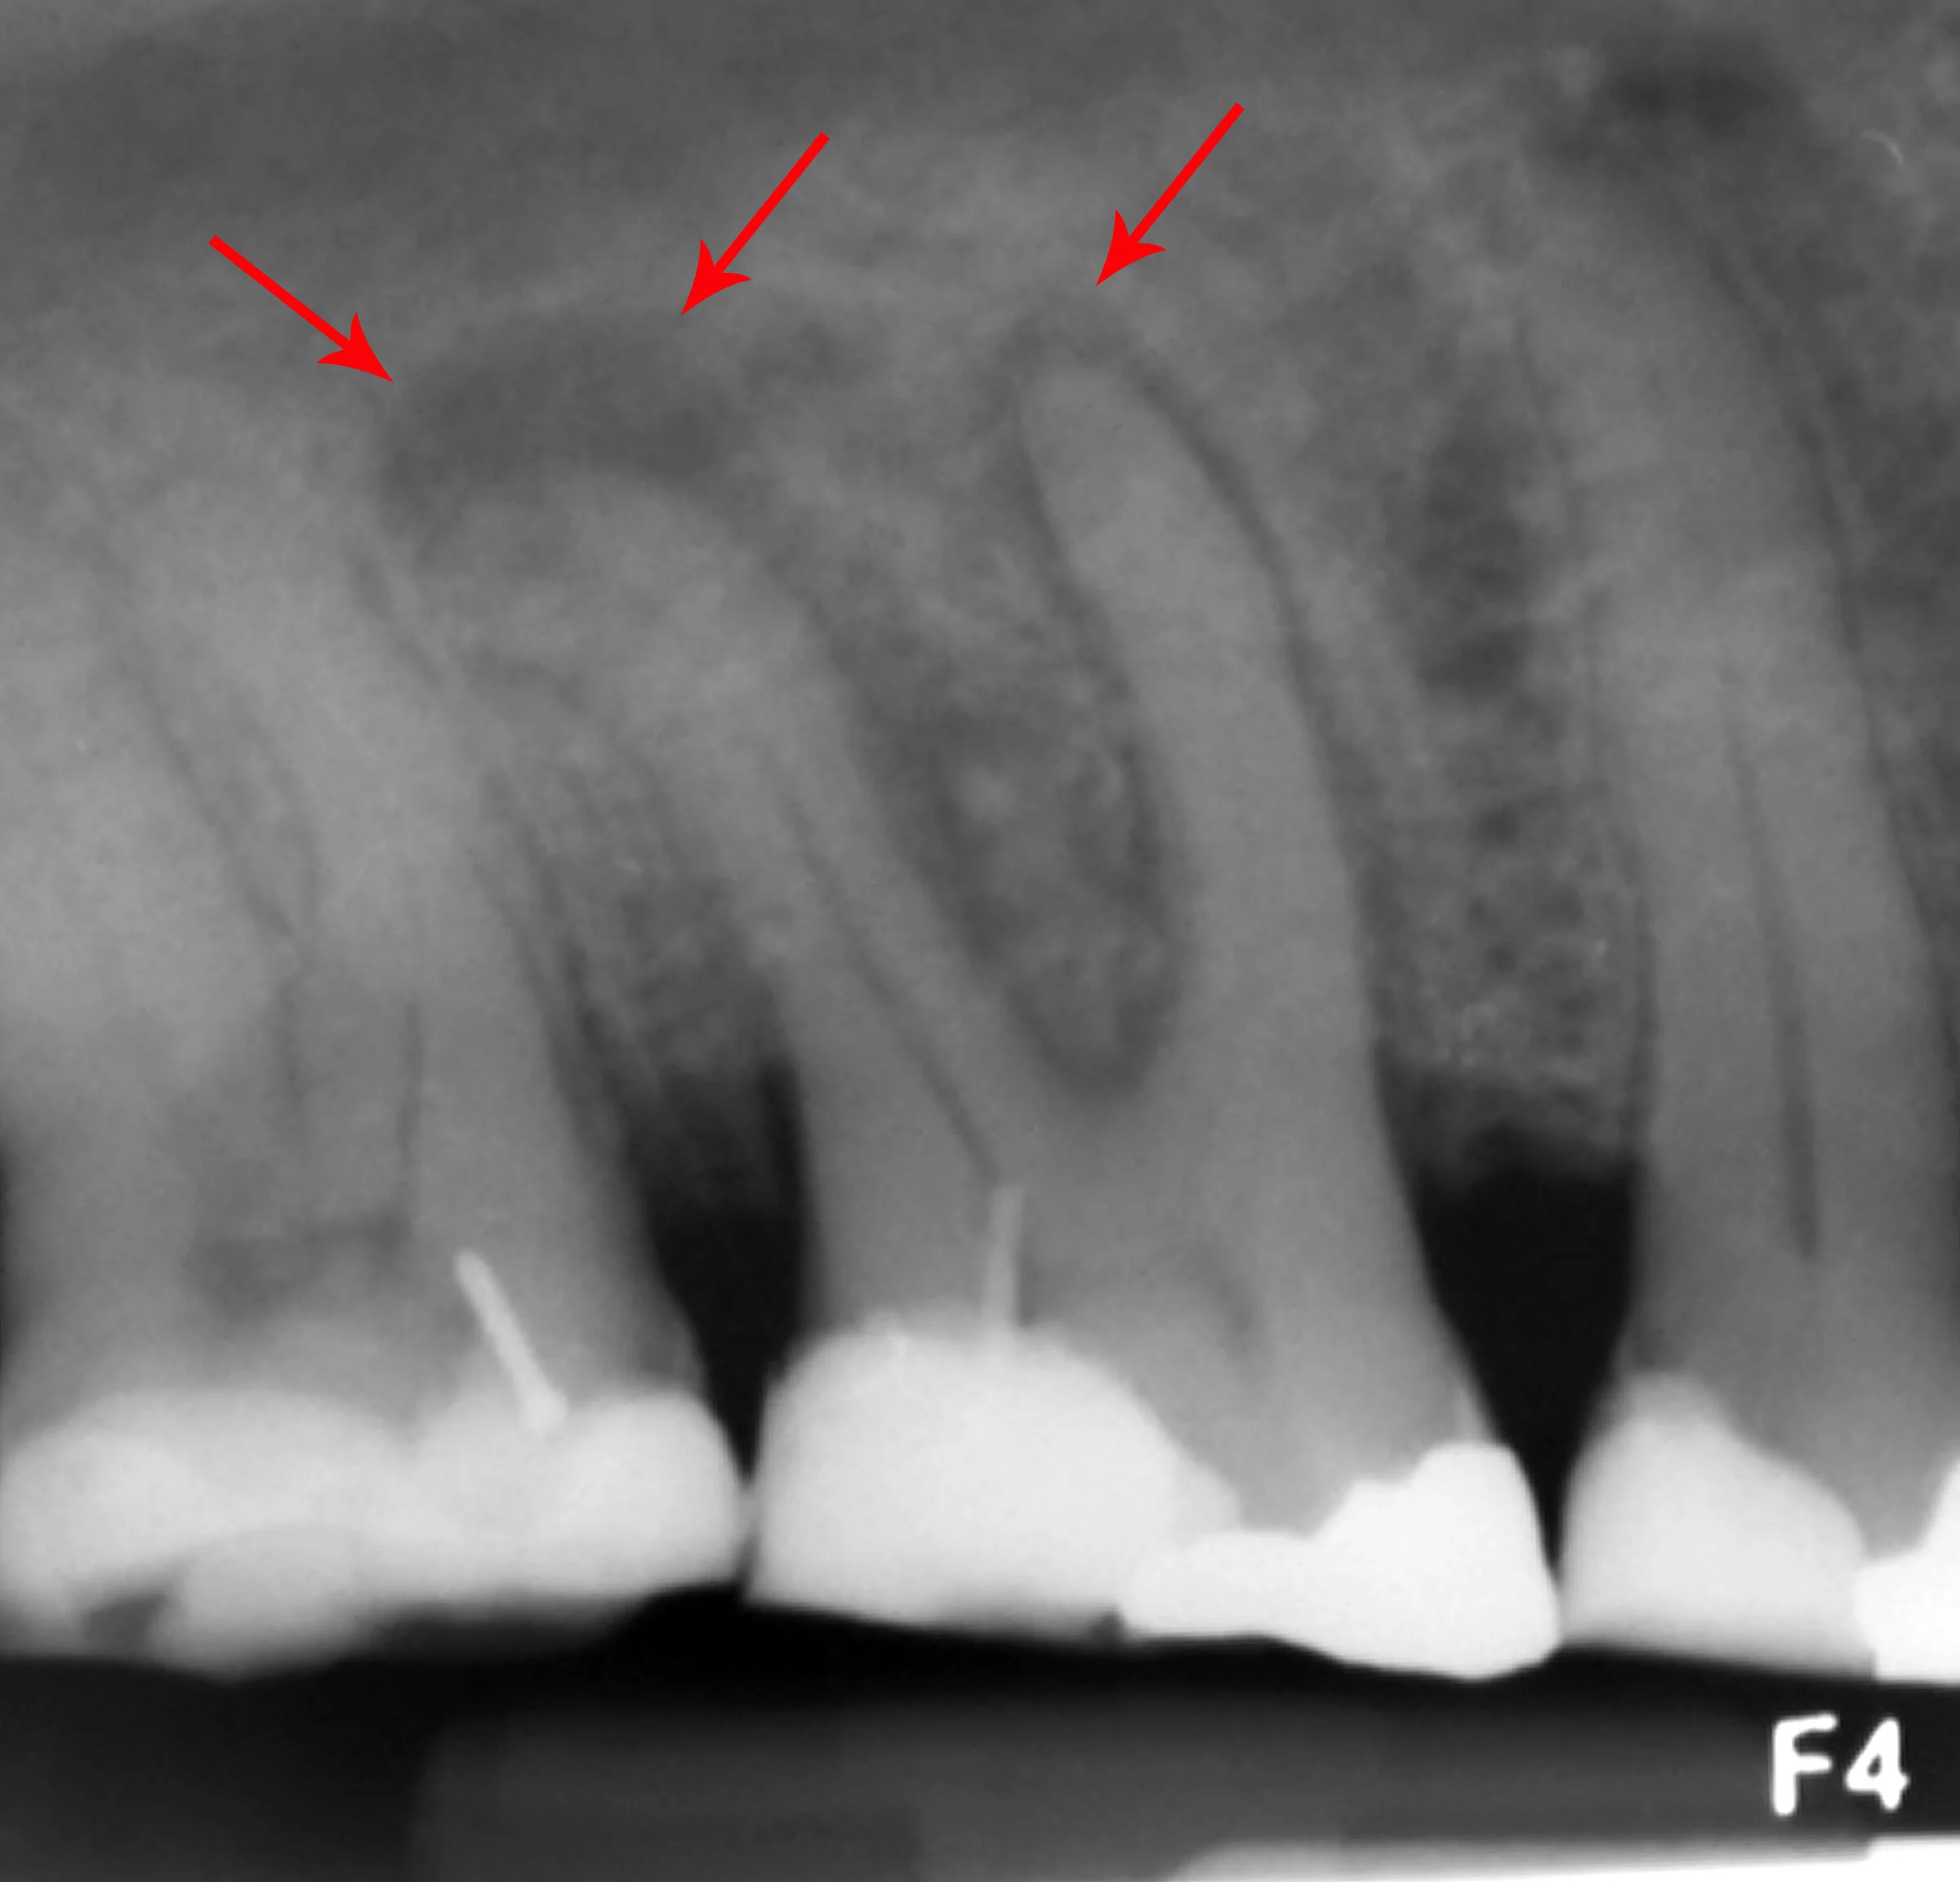

Нарыв Зуба Фото

Нарыв Зуба Фото 114 фотографий